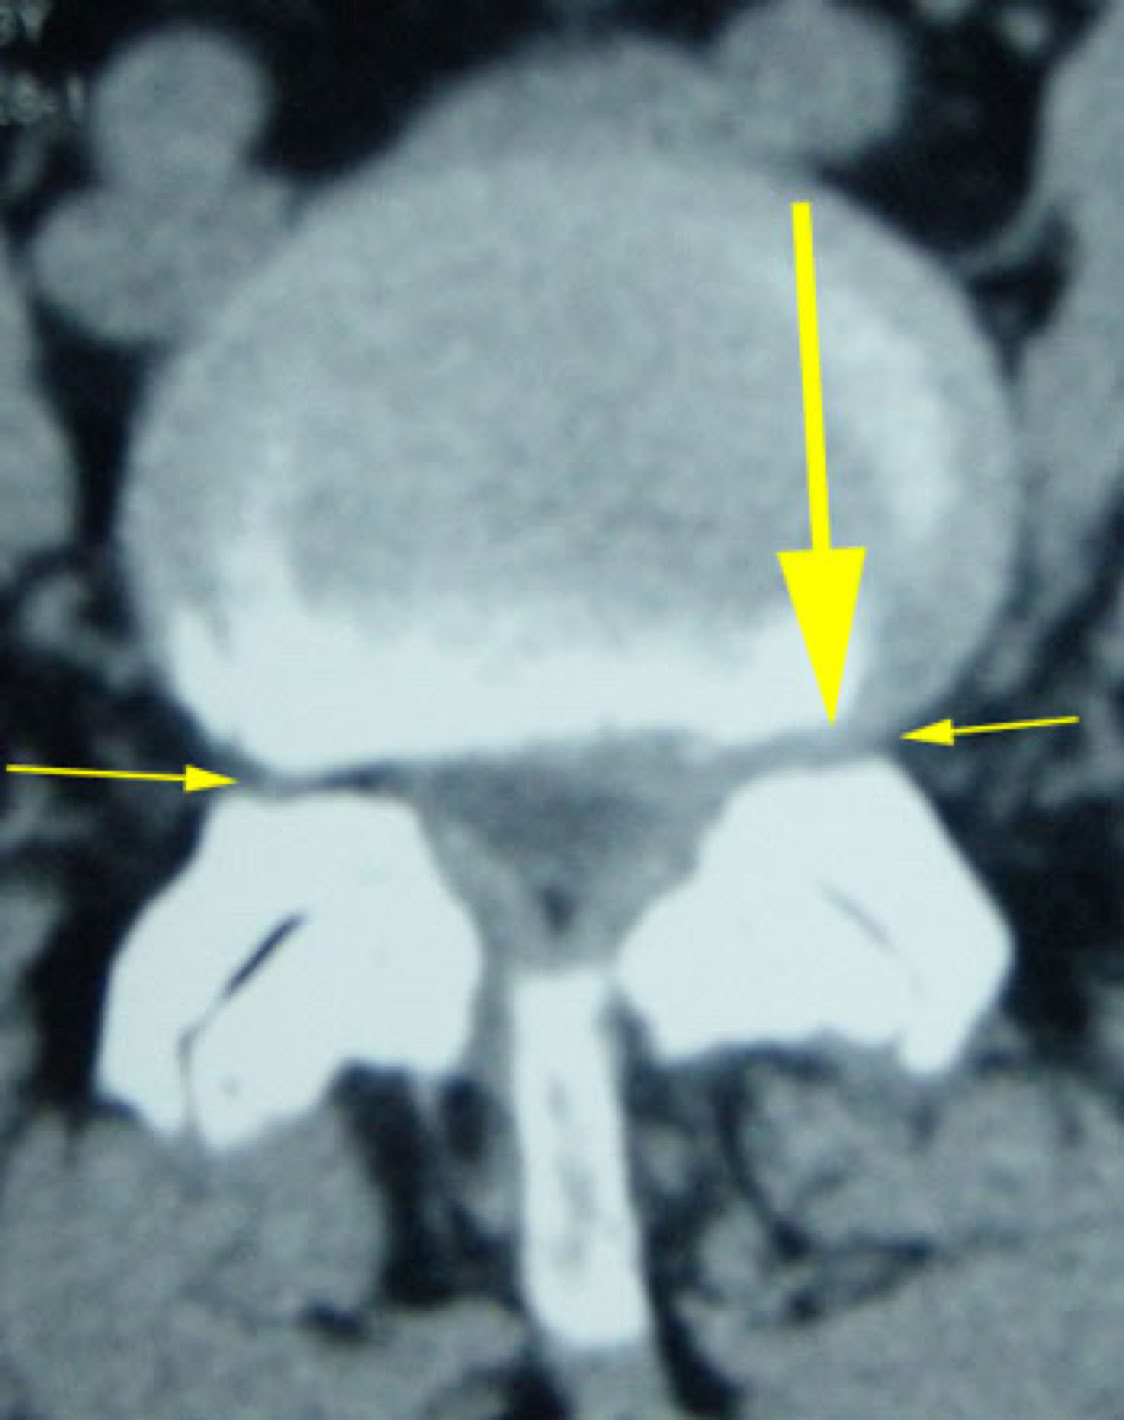

The new MRI was NORMAL. The previously reported large L4-5 disc was completely resorbed. (see picture below)